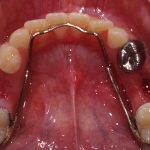

We at the Department of Pediatric & Preventive Dentistry focus on comprehensive oral health care needs of a child from infancy to adulthood and provide comprehensive, therapeutic as well as preventive care to all children including those with special care needs.

Treatment and Services